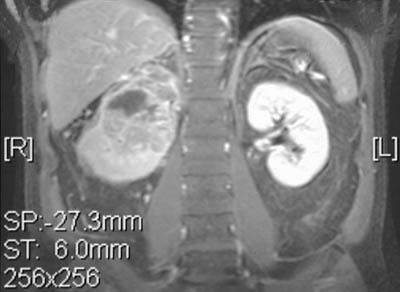

These T1 weighted coronal MRI scans reveal a renal cell carcinoma of the left kidney, with post-gadolinium enhancement above highlighting the cystic and solid components.